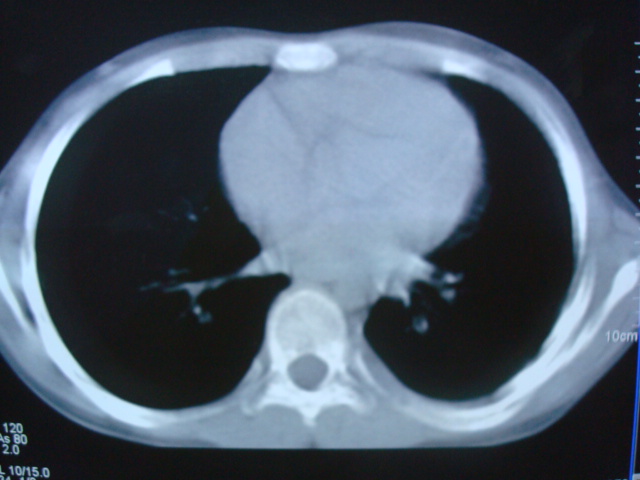

标题: PED0869:男,10岁,肺内多发结节+胸水 [打印本页]

标题: PED0869:男,10岁,肺内多发结节+胸水

男,10岁,左胸痛,发热轻,血象高。后到省级权威医院治疗,病情明显好转,结果几天后公布。老机器,图像质量差,见谅。

考虑血源性肺脓肿或韦氏肉芽肿

考虑血源性肺脓肿